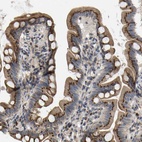

Immunohistochemical staining of human small intestine shows strong cytoplasmic positivity in glandular cells.